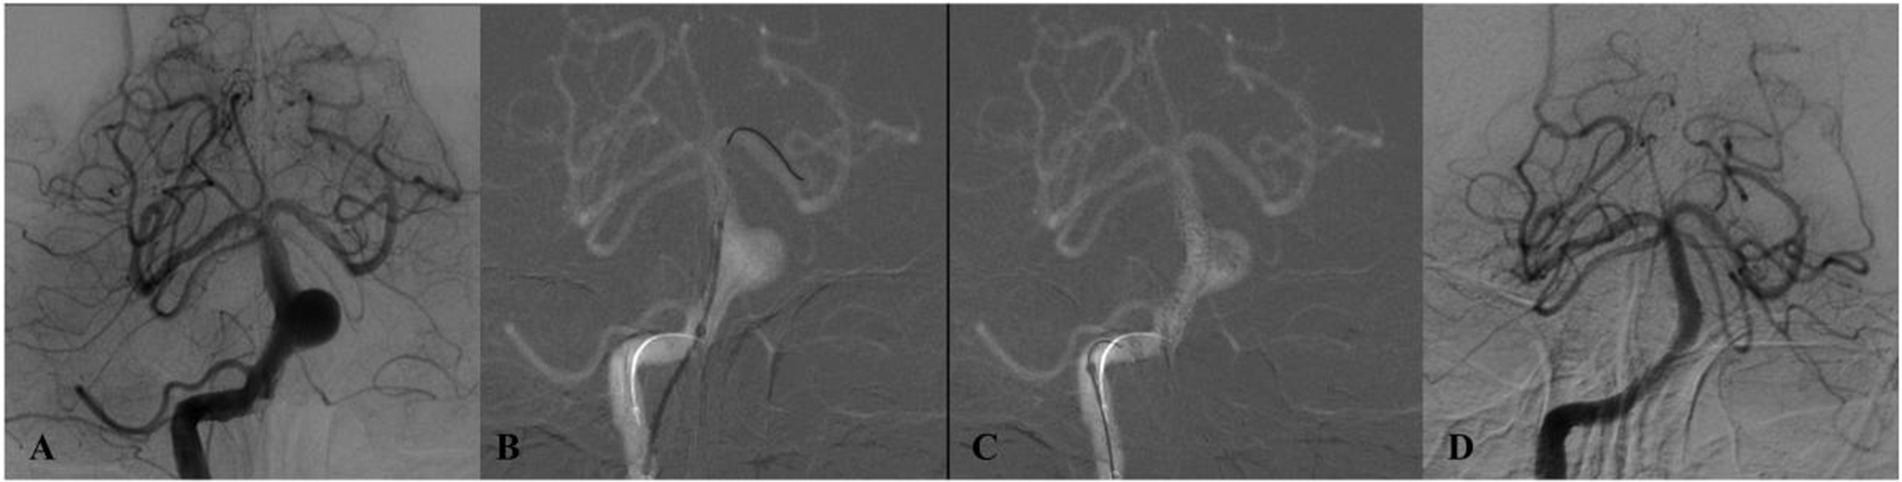

Four-panel angiographic images labeled A to D show different views of cerebral vasculature. Panel A depicts an aneurysm, Panel B shows a coiled vessel, Panel C presents a frontal view of complex vessel patterns, and Panel D displays a post-treatment vessel structure.

Figure 3. DSA of a patient from the 65–69 age group (Case 3) with dizziness. (A) Initial angiogram shows a giant basilar trunk aneurysm measuring 15 × 14 mm. (B,C) Post-treatment lateral and anteroposterior projections after implantation of a single Tubridge flow diverter. (D) 10-month follow-up DSA reveals durable, complete occlusion.